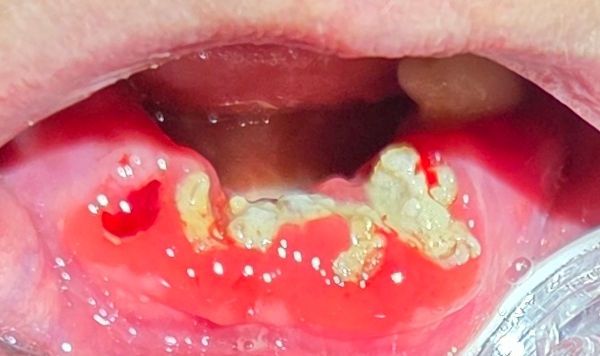

Diese Patientin ist in einem Demenzheim. Sie schläft nur noch regungslos in einem Bett. Dabei atmet sie meistens mit offenem Mund. Vielleicht ist das eine starke Nebenwirkung von Risperidone, einem Medikament gegen Schizophrenie. Die Pflegerin kann ihr die Zähne nicht putzen, weil dann das Zahnfleisch stark zu bluten beginnt.

In einem trockenen Mund entsteht jeweils viel Karies, weil die Abwehrstoffe des Speichels gegen die Zahnbeläge fehlen. Zwar würden wenigstens die Zungenbewegungen eine gewisse "Selbstreinigung der Zähne" bewirken. Aber bei dieser Patientin ist offensichtlich auch die Zunge regungslos geworden.

Bange fragt man sich, wird nicht auch das Herz bald einschlafen?